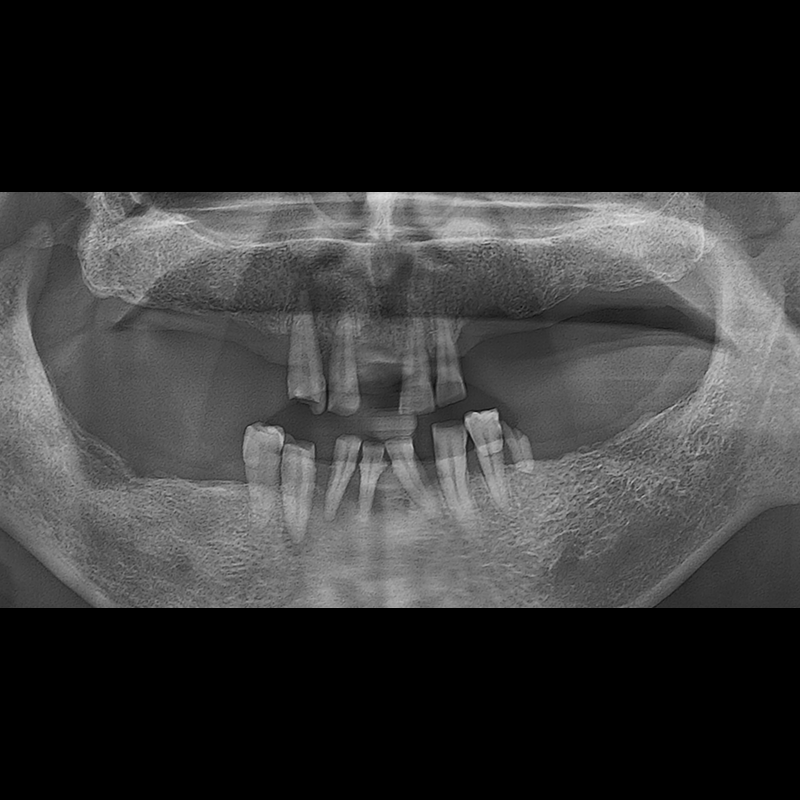

IMPLANT

BEFORE AFTER